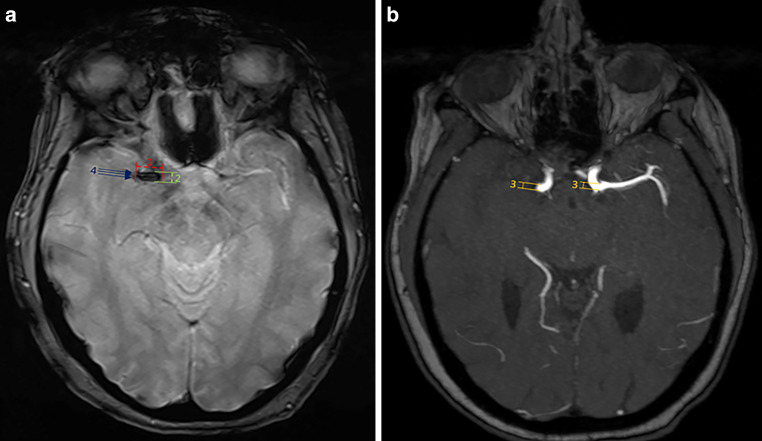

Background: The susceptibility vessel sign (SVS) on baseline MRI in acute ischemic stroke patients has been associated with better outcomes post-thrombectomy. This study aimed to investigate whether the presence of the SVS modifies the treatment effect of intravenous thrombolysis plus endovascular thrombectomy (IVT + EVT) versus thrombectomy alone (EVT alone).

Methods: In this secondary analysis of the SWIFT DIRECT trial, comparing IVT + EVT versus EVT alone, treatment effect and its heterogeneity were assessed with rates of pre-interventional reperfusion (eTICI 2a-3) and successful post-interventional reperfusion (eTICI of 2b-3) according to the SVS status using adjusted multivariable logistic regression. Secondary objectives were to analyze whether the presence of SVS or its individual characteristics (location, length, width, overestimation ratio, two-layered sign) were associated with outcomes.

Results: 197 of the initial 408 trial participants were included in this secondary analysis, of which 52% received IVT + EVT. SVS was present in 92% of the participants (n = 181). There was no evidence for treatment effect heterogeneity regarding the post-interventional radiological and clinical effects of IVT + EVT versus EVT alone with strata of SVS. In SVS+ participants, IVT favored pre-interventional reperfusion (aOR 7.95, 95% CI 1.42-44.46), whereas in SVS-patients, it did not (P for interaction = 0.02). The individual SVS characteristics showed no significant associations with outcomes.

Conclusion: Presence of SVS does not seem to modify the effect of IVT + EVT versus EVT alone. In SVS+ patients, IVT might improve pre-interventional reperfusion. There is insufficient evidence to recommend using SVS to inform IVT decisions prior to EVT.